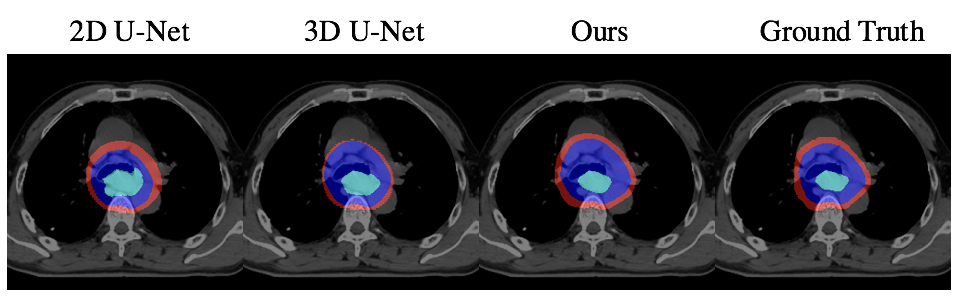

To evaluate our method, we chose the most commonly used CNN-based segmentation frameworks: 2D U-Net[8] and 3D U-Net[4] as our baselines. Since we focus on predicting the accurate radiotherapy target contouring, we trained and tested with valid slices that contain tumors. That is, given the volume where oncologists want to deliver radiation, we are able to segment the GTV, CTV and PTV regions precisely. For quantitative comparison, following metrics in [5], we use DSC, Sensitivity, and Specificity and ran with five-fold cross-validation. Table. 1 and Figure. 2 shows that our non-interactive method outperforms all the baselines both qualitatively and quantitatively. In the interactive setting, the results are evaluated on the selected sequences with “min median DSC” of GTV for each patient, in the exclusion of the slice we have reconstructed the features. As shown in Table. 2, the results are further improved after the interaction.